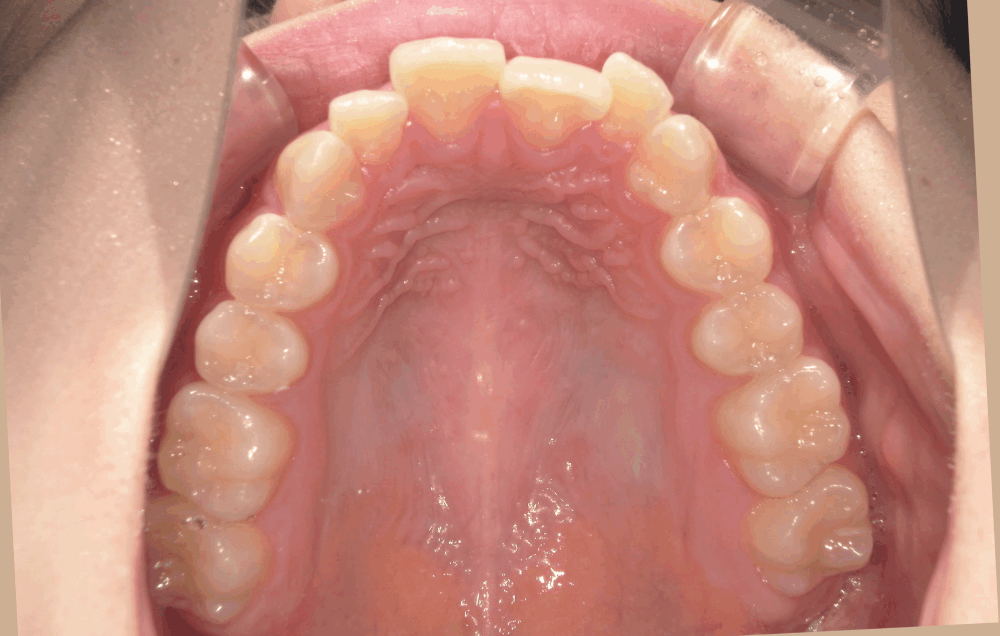

<初診時>

上の前歯の横の歯(前から2番目)が前方に飛び出しており、全体的にガタつき(叢生)が見られます。これは、歯の大きさに対してあごの幅がやや狭く、歯がきれいに並ぶスペースが足りないために起こります。

- 中程度の叢生(ガタガタ)

また、奥歯の噛み合わせがずれていたことで、全体的に歯が並ぶスペースが不足しており、叢生も生じていました。